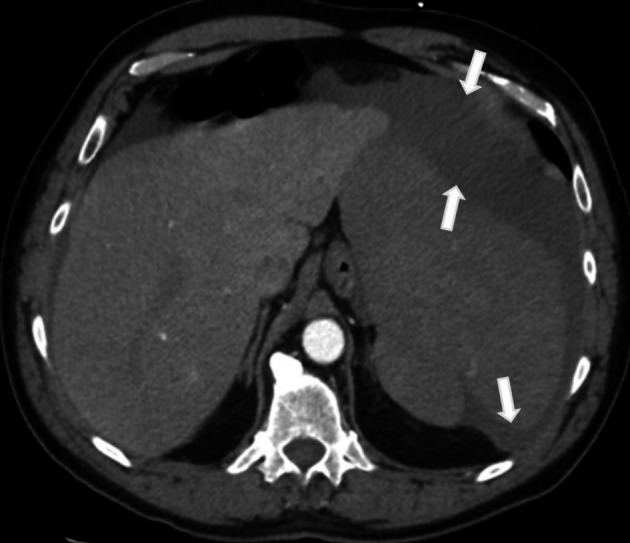

We present the case of a 64-year-old man who suffered a splenic rupture following a fall. A peripheral blood smear showed mononuclear cells with "hairy" cytoplasmic projections. A computed tomography (CT) angiogram revealed splenomegaly with a hematoma and active contrast extravasation. He underwent coil embolization of the splenic artery but subsequently developed worsening abdominal pain and ileus, requiring a splenectomy. Pathological examination of the spleen showed extensive infiltration by hairy cell leukemia (HCL). Bone marrow biopsy revealed hypercellular marrow predominantly infiltrated by HCL cells positive for CD20, CD103, and the BRAF V600E mutation. After the splenectomy, pancytopenia gradually improved. The symptoms of the patient, such as fatigue, weight loss, and night sweats, were also resolved. Circulating HCL cells were significantly reduced, and the "hairy" morphology became smoother. To our knowledge, this morphologic change of the hairy cells after splenectomy has not been reported in the past. Its mechanism is not known. We postulate that splenectomy may induce molecular or immunological changes that alter HCL cell behavior, which warrants further research.